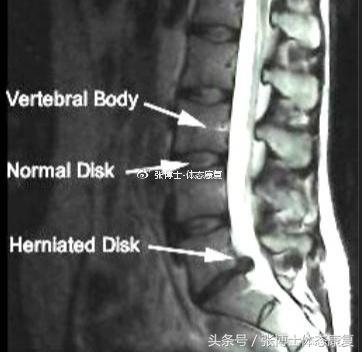

人体的脊柱,由一个个椎体组成的。每个椎体之间有一个椎间盘,厚8~10毫米,上下两面是椎体的软骨面,中央有胶状的髓核,四周包着致密的纤维环。纤维环相当坚韧,髓核不易向四周移动。椎间盘纤维环和髓核均含有丰富水分,具有良好弹性,可随脊柱所受压力而变化。当上下压力增加时,髓核就会变扁,向四周膨出。

腰椎间盘突出症是指腰椎间盘纤维环破裂,髓核组织从破裂之处突出(或脱出)于后方或椎管内,导致相邻脊神经根遭受刺激或压迫,从而产生腰部疼痛,一侧下肢或双下肢麻木、疼痛等一系列临床症状。

年轻人椎间盘含水分多,弹性好,周期性生理变化颇明显。椎间盘没有直接的血液供应,靠四周和上下软骨给它渗透营养。如果负重大,活动多,髓核和纤维环就会早早发生退变。髓核和纤维环含水量下降,弹性降低,椎间盘向四周均匀扩大,这就形成了椎间盘膨出。

腰间盘突出一般是因为椎间盘以及腰椎发生退行性病变,椎间盘含水量变少,周围肌肉韧带失去弹性,变得比较松弛。腰椎的平衡性大大降低,当腰椎经受到外界作用力时,椎间盘所受压力升高,从而破坏了椎间盘周围的纤维环,髓核的形状位置发生改变,导致神经根被改变了位置的椎间盘压迫。周围组织因为炎症血流不畅等原因导致粘连肥厚、水肿,致使神经根容易受到刺激,使其相对应的肢体支配区的运动、感觉以及反射功能发生明显的感应变化。